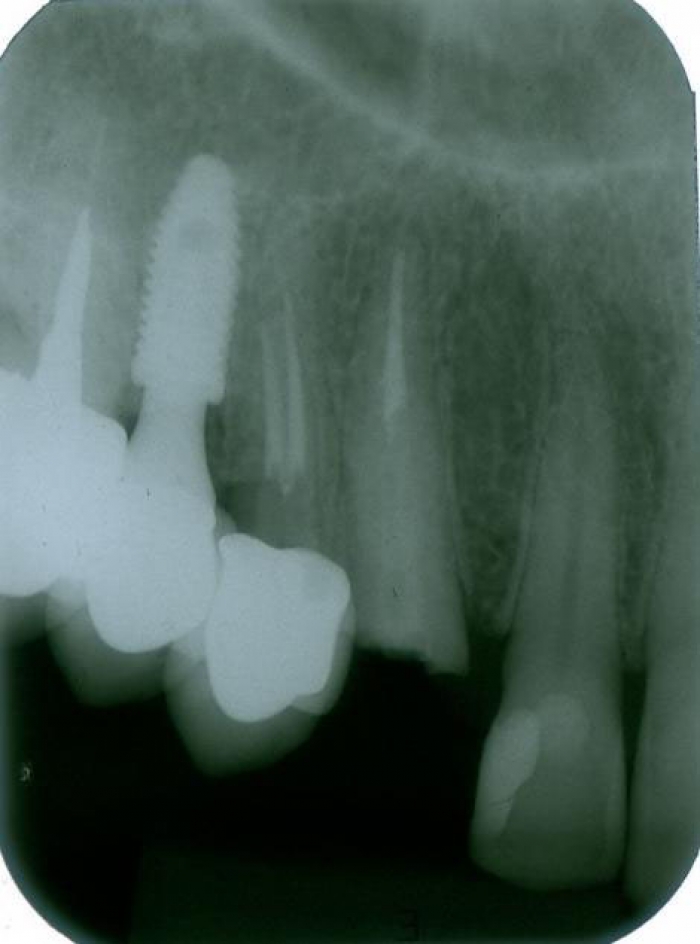

Rx Periapical Pré-cirurgico 03-10-16 - Clínica Cliniface

Rx Periapical Pré-cirurgico 03-10-16